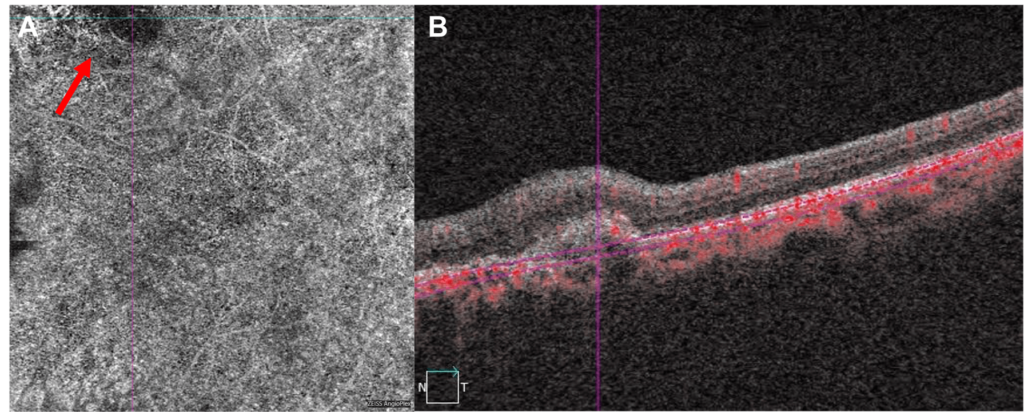

Figure 1 OCT - An image of the superficial choroid. (a) En face image depicting a MNV lesion (red arrow). (b) corresponding B-scan image showing segmentation lines and flow signals.

84-year-old male with age related macular degeneration (ARMD) presented 5 days after suddenly losing central vision OS. Medical history was significant for hypertension and benign prostate hypertrophy. Best corrected visual acuity (BCVA) measured 20/30 OD and counting fingers OS. Anterior segments were unremarkable except for PCIOL OU. A large submacular hemorrhage (SMH) OS was visualized measuring 6.0 x 3.75 x 1.0 mm (Figure 1). Macular optical coherence tomography (OCT) revealed thickening with hyper & hyporeflective subretinal material (Figure 1B). Preoperative intravitreal bevacizumab (IVB) and subsequent vitrectomy surgery was performed with subretinal tissue plasminogen activator (rTPA) delivery and gas exchange. BCVA improved to 20/60 two months postoperatively with resolution of the hemorrhage and some resultant thinning and irregularity in the outer nuclear and ellipsoid photoreceptor layers (Figure 1C). Regular IVB was continued postoperatively for the extrafoveal macular neovascularization (MNV) process (Figure 2).